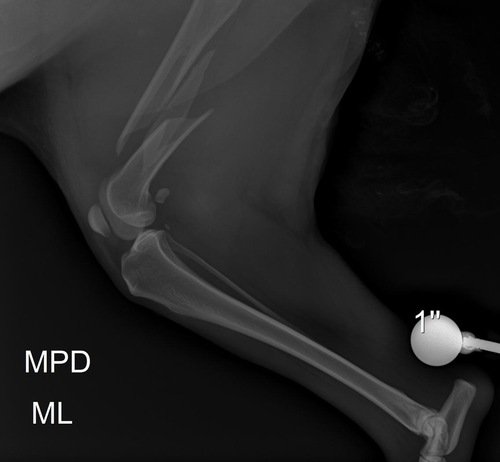

Essa é a Rute, foi atropelada na segunda feira de carnaval, foi resgatada porém não temos o valor para fazer a cirurgia, ela teve múltiplas fraturas e uma bem grave com risco de se tornar exposta!! Precisamos muito da ajuda de todos vocês para que a Rute possa ser operada o mais rápido possível..